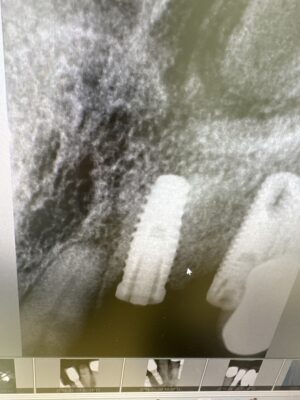

Case here for a maxillary partial overdenture. How do these positions look prosthetically in respect to their existing partial? I placed them as best I could. Also how far subcrestal should I am for? 1-2mm?